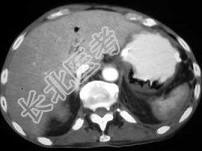

- 单项选择题急腹症患者,结合图像, 最可能的诊断为 ( )

A、结肠积气症

B、胃幽门梗阻

C、气肿性胃炎

D、胃癌

E、以上都不是